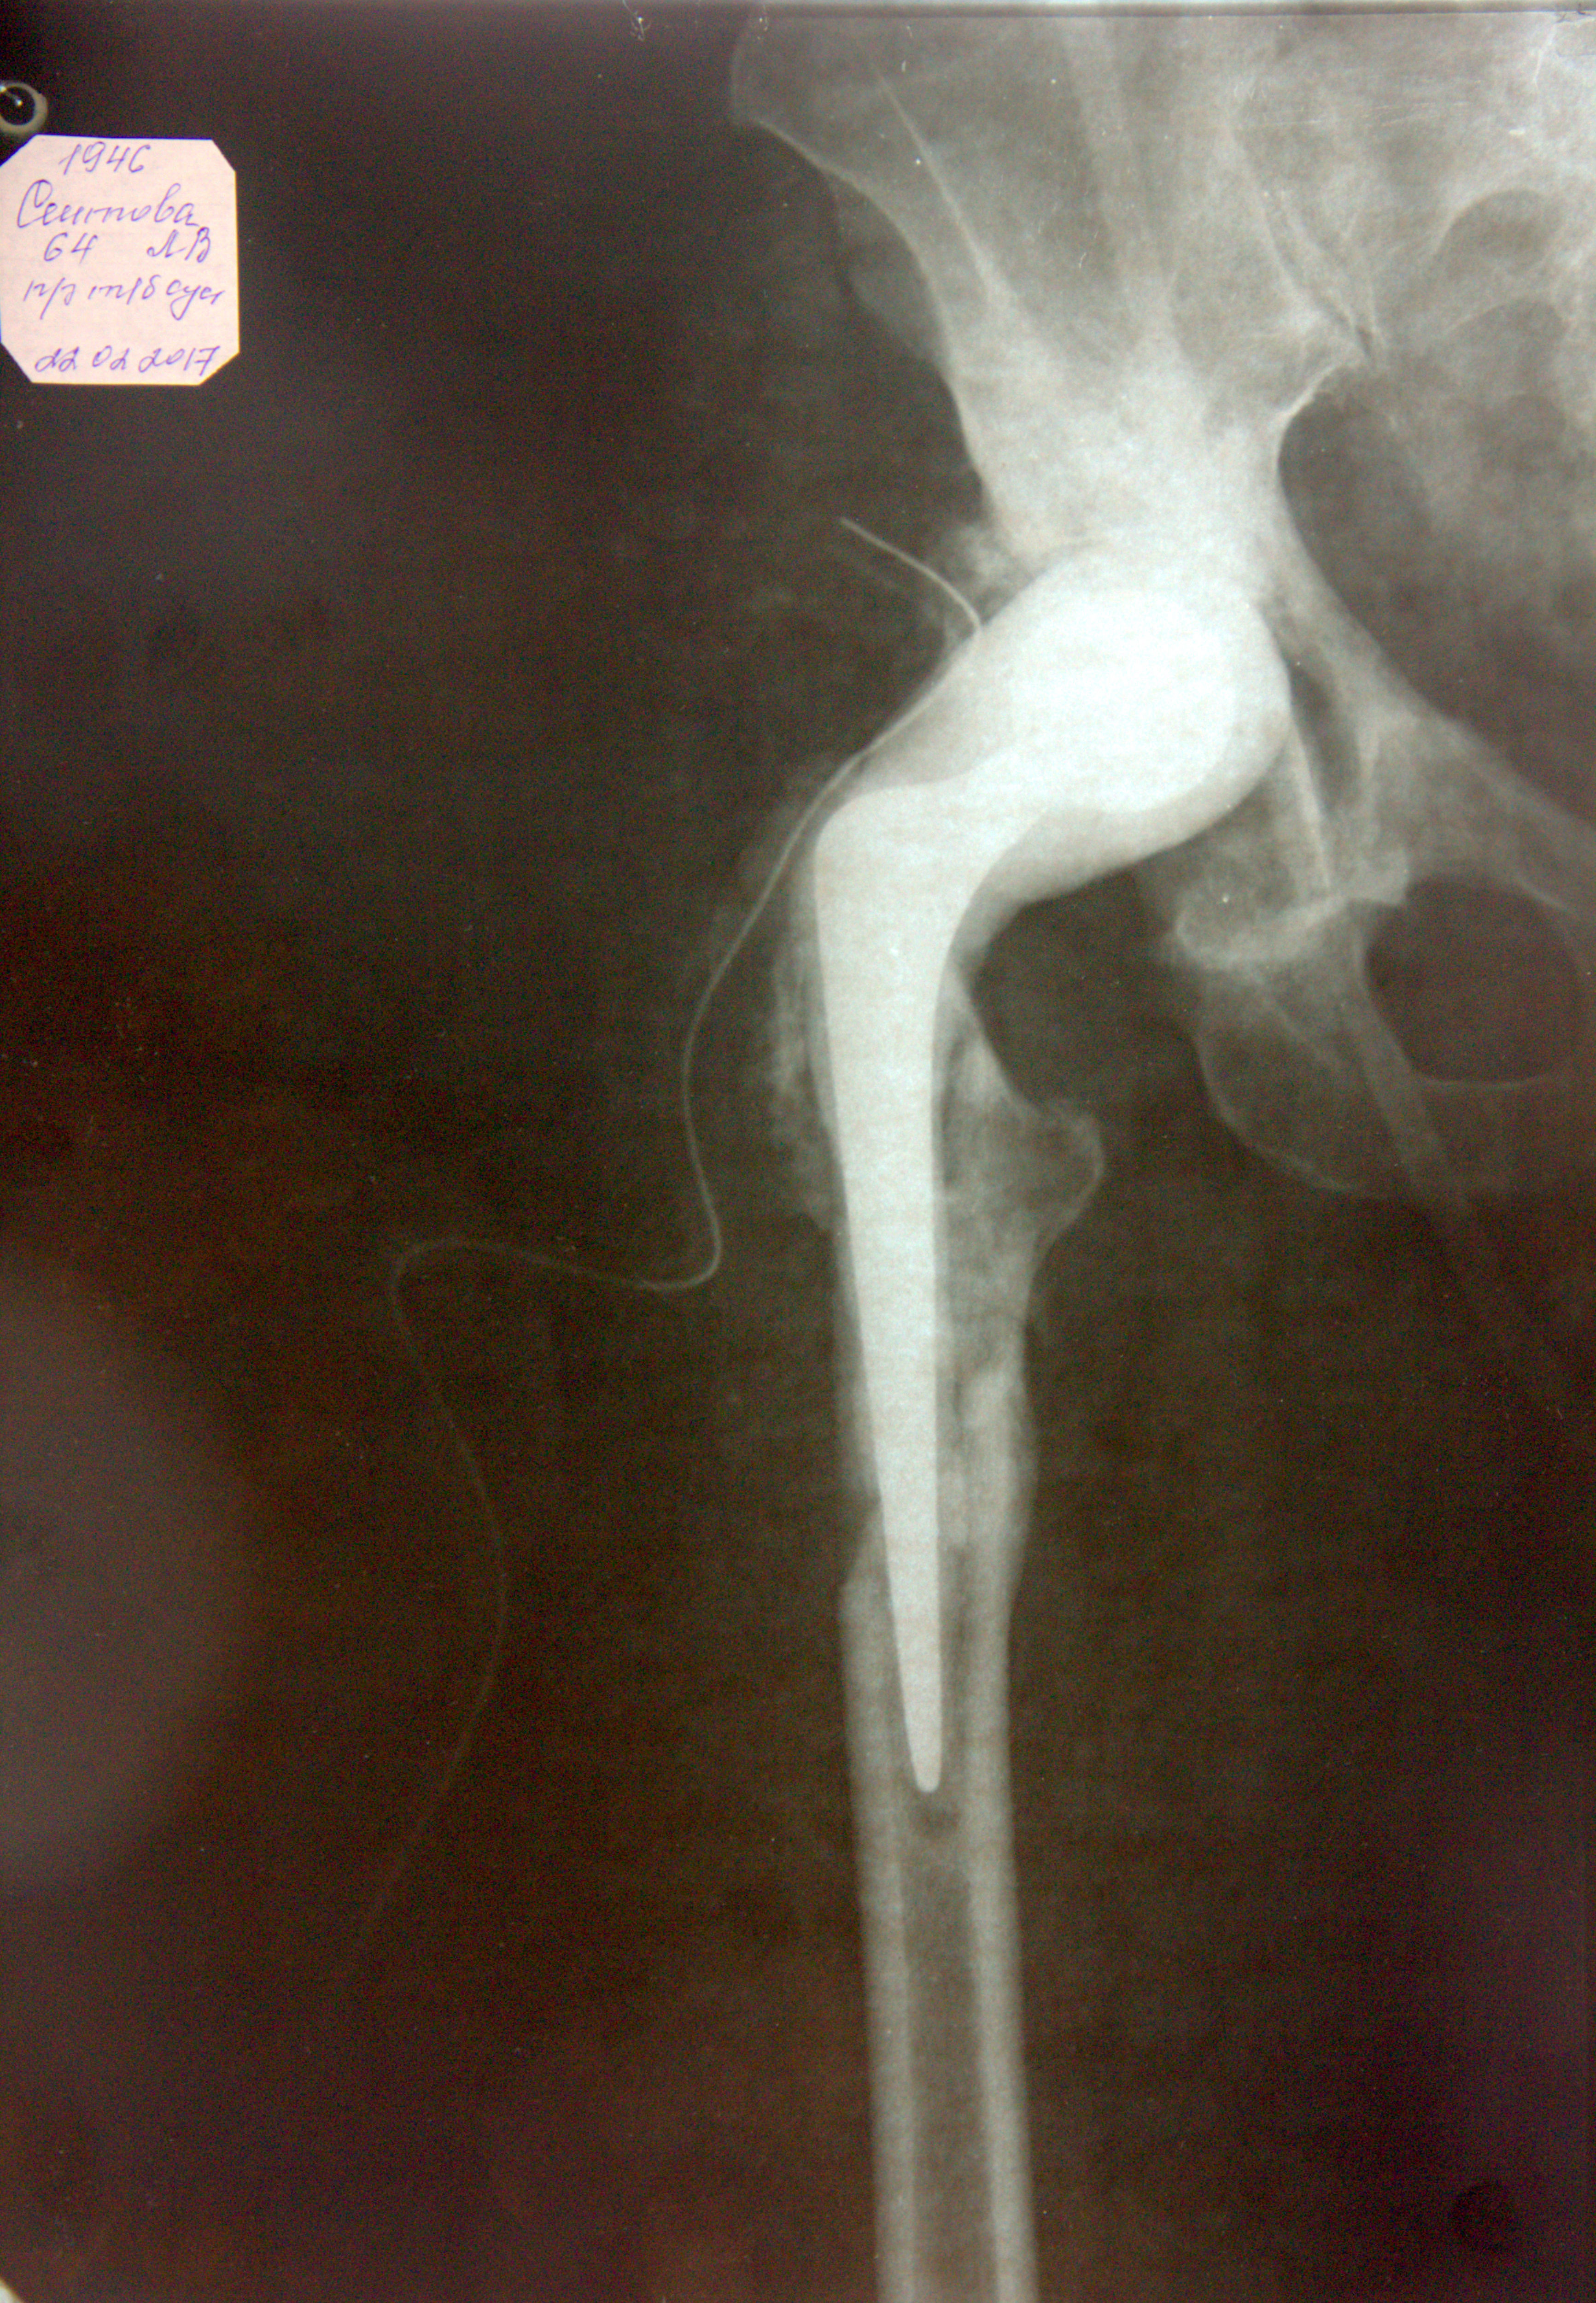

Добрый день. Мне сделано 2 операции по эндопротезированию и 1 операция ревизионное эндопротезирование т\б суставов в 2001, 2003, 2009гг в ГКБ-13 г. Москва.( платно) 21.02.17 г в Дорожной больнице Ярославля выполнена ревизия области правого т\б сустава, удалены компоненты эндопротеза и установлен цементный префармованный артикулирующий спейсер с антибиотиком . Спейсер не закреплен, во время операции сломлена бедренная кость. Сейчас уже второй месяц нахожусь в лежачем положении, могу с трудом пройти с помощью ходунков 10 м. В Архангельске операцию сделать не могут, из-за отсутствия оборудования. Сказали, что операцию могут в РФ выполнить несколько человек только в специализированных центрах. Посоветовали обратиться в РНИИТО им Вредена г. Санкт- Петербурга. Документы на квоту на ВМП оформили, но очередь ждать три года.. А спейсер устанавливают на 3-4 мес, т.. е..в конце мая , июне надо устанавливать эндопротез. Три года со спейсером я просто не могу лежать. Очень надеюсь на Вашу помощь с уважением Архангельск, Людмила Валентиновна